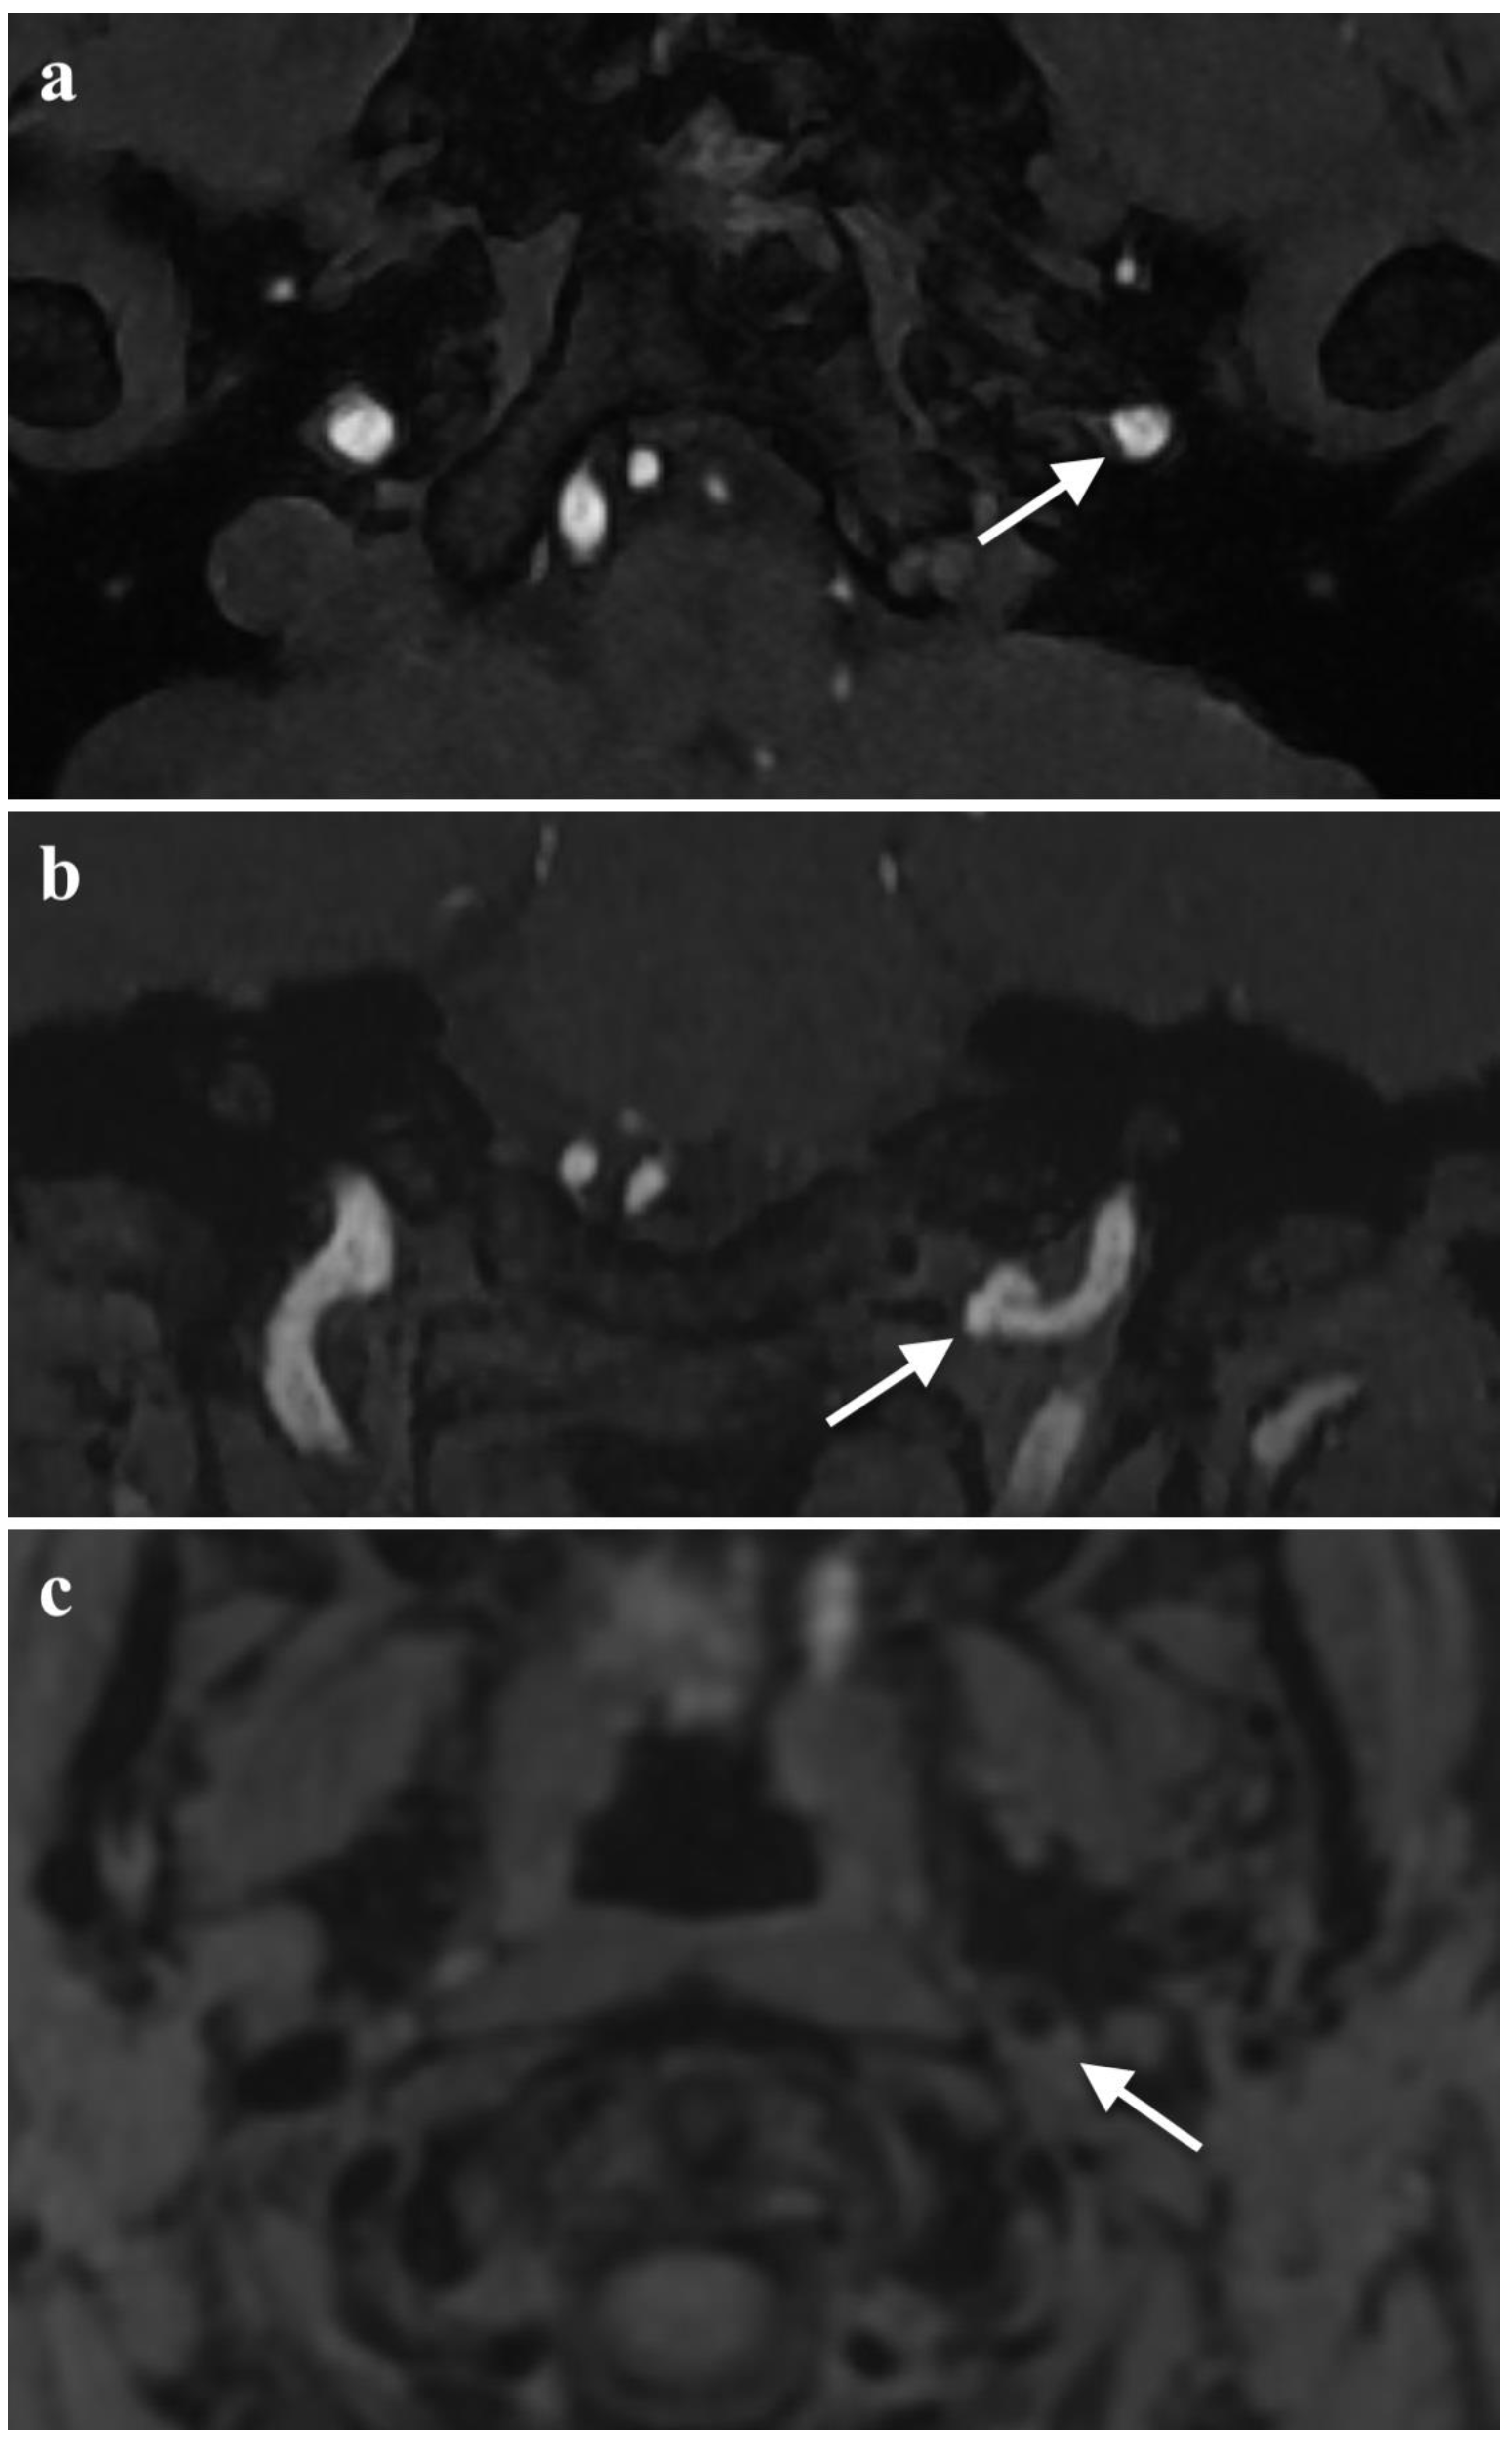

2. Case Presentation

2.2. Diagnosis